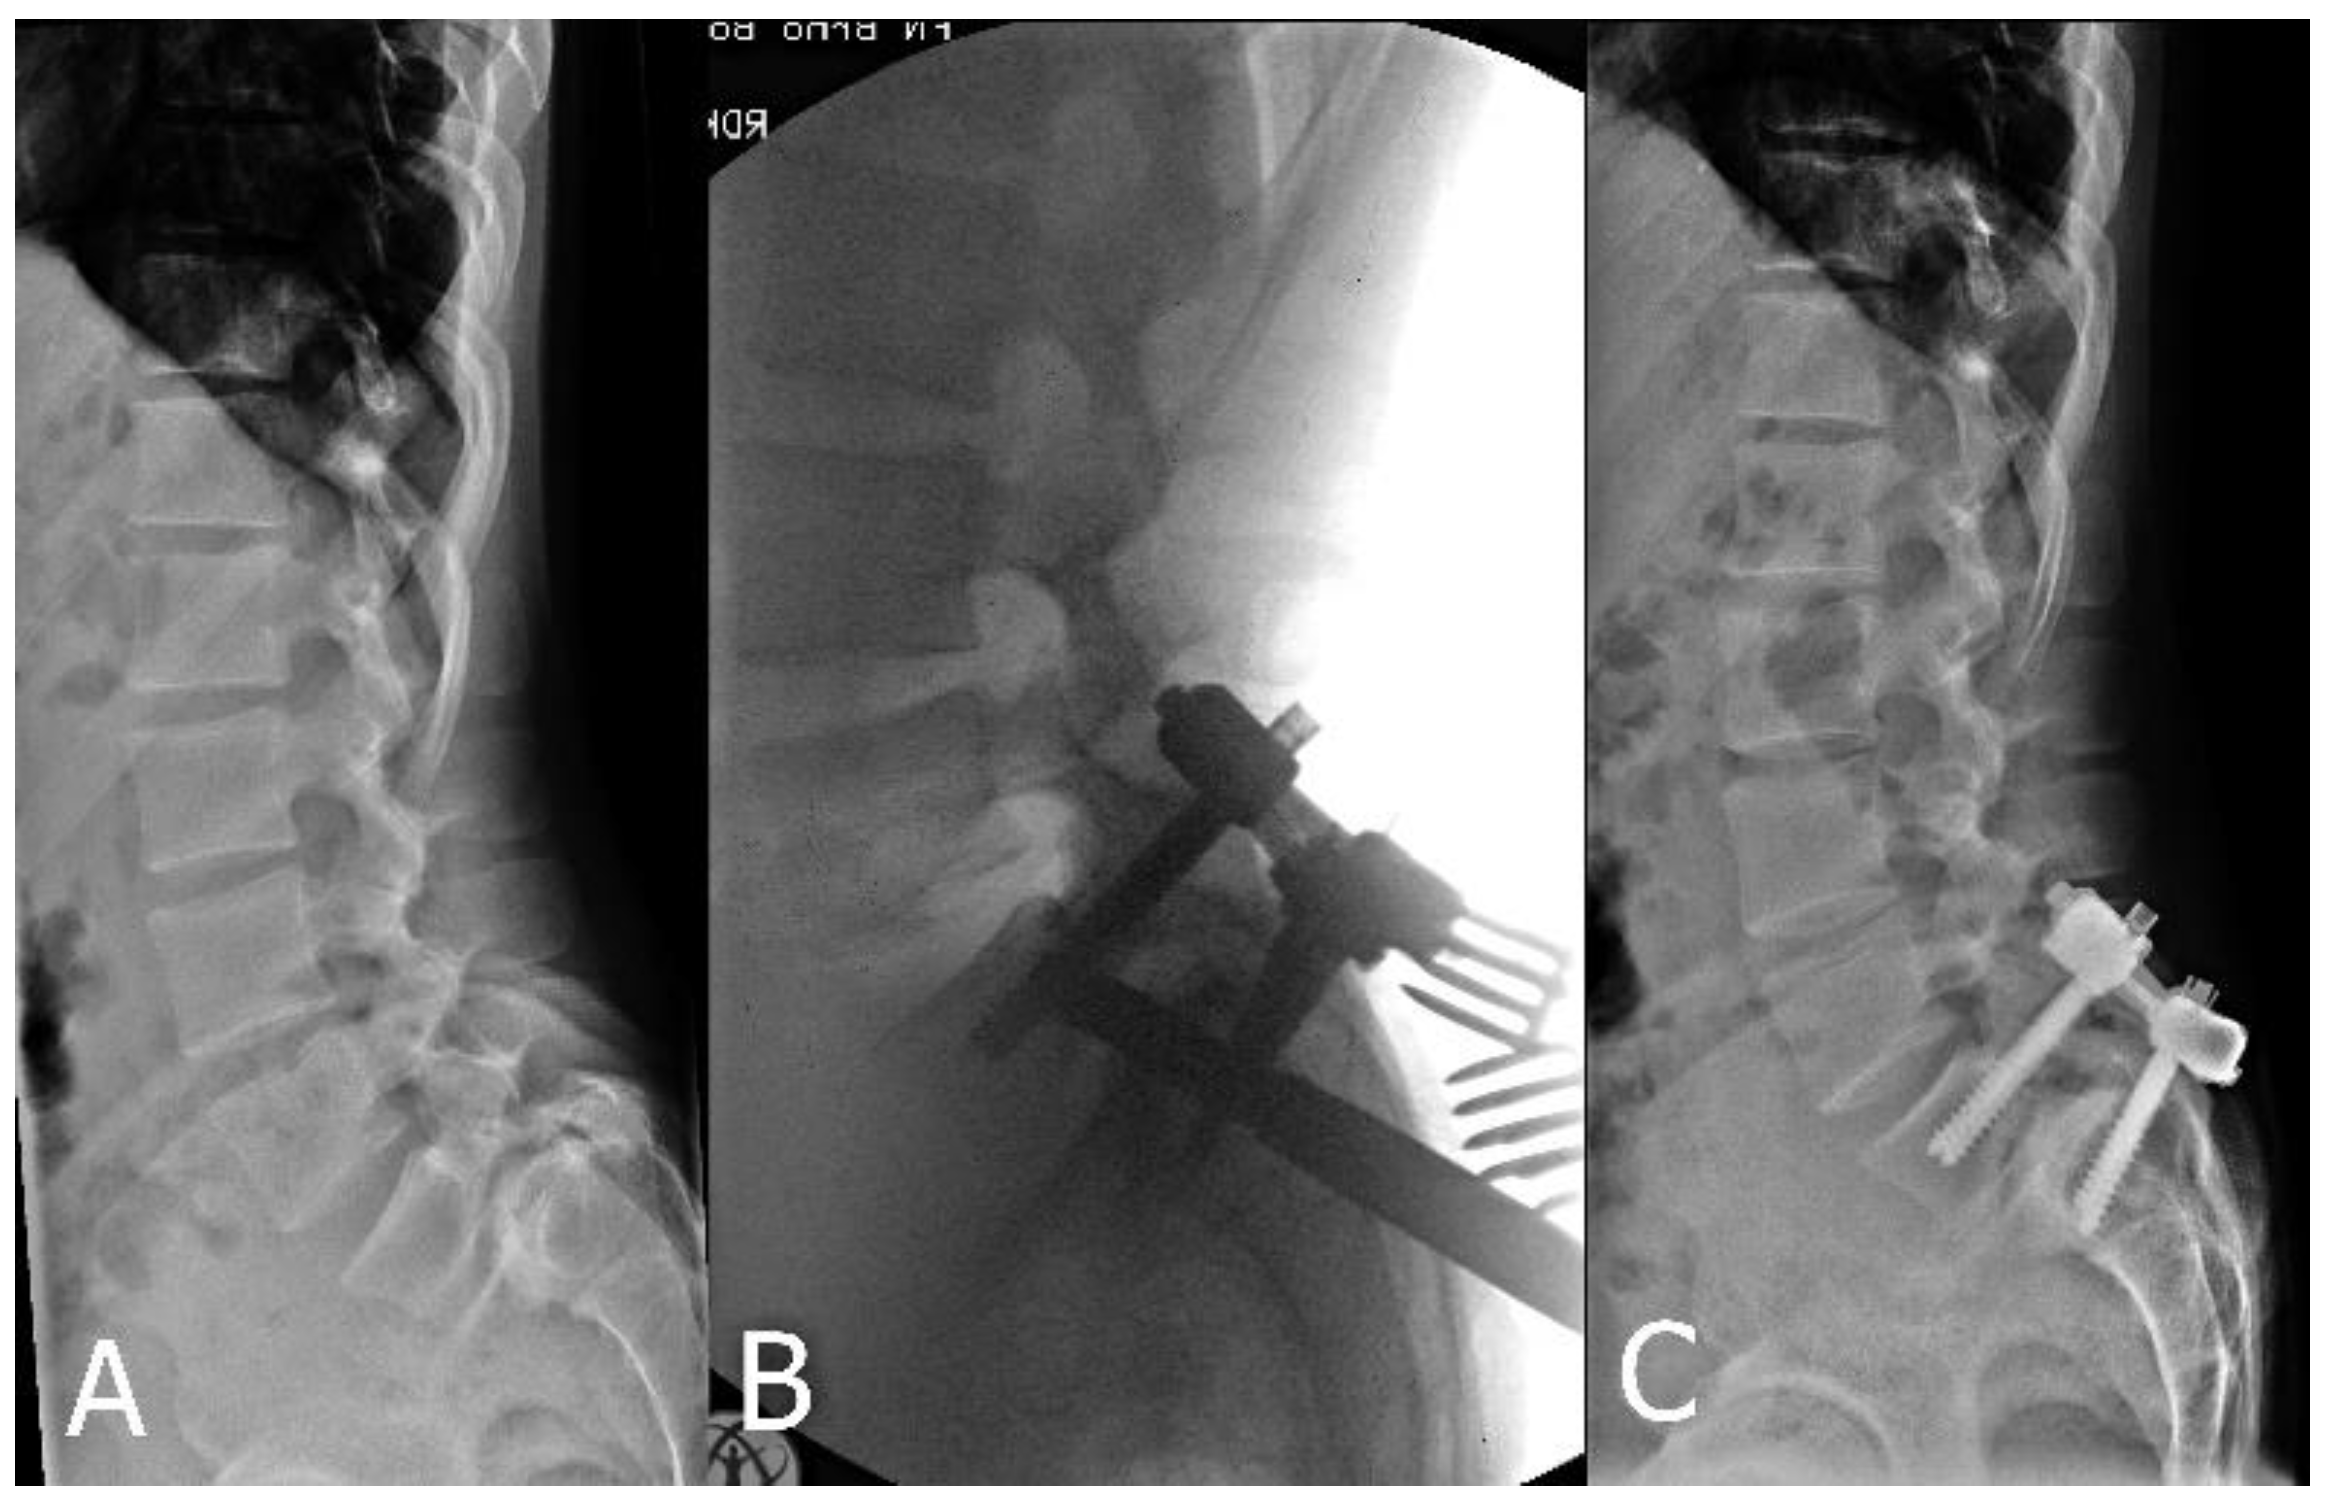

2.2. Surgical Technique

2.2.1. Posterior Approach Only

2.2.2. Combination of Posterior and Anterior Approaches